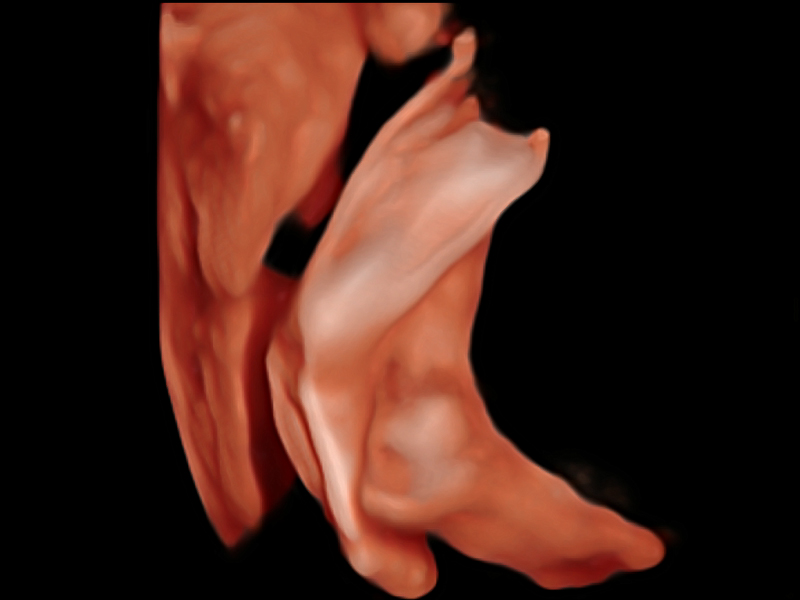

新一代微米成像技术大大提高了器官和病变的可见性。高清对比度分辨率将抑制斑点噪声,同时保持真实的组织结构。